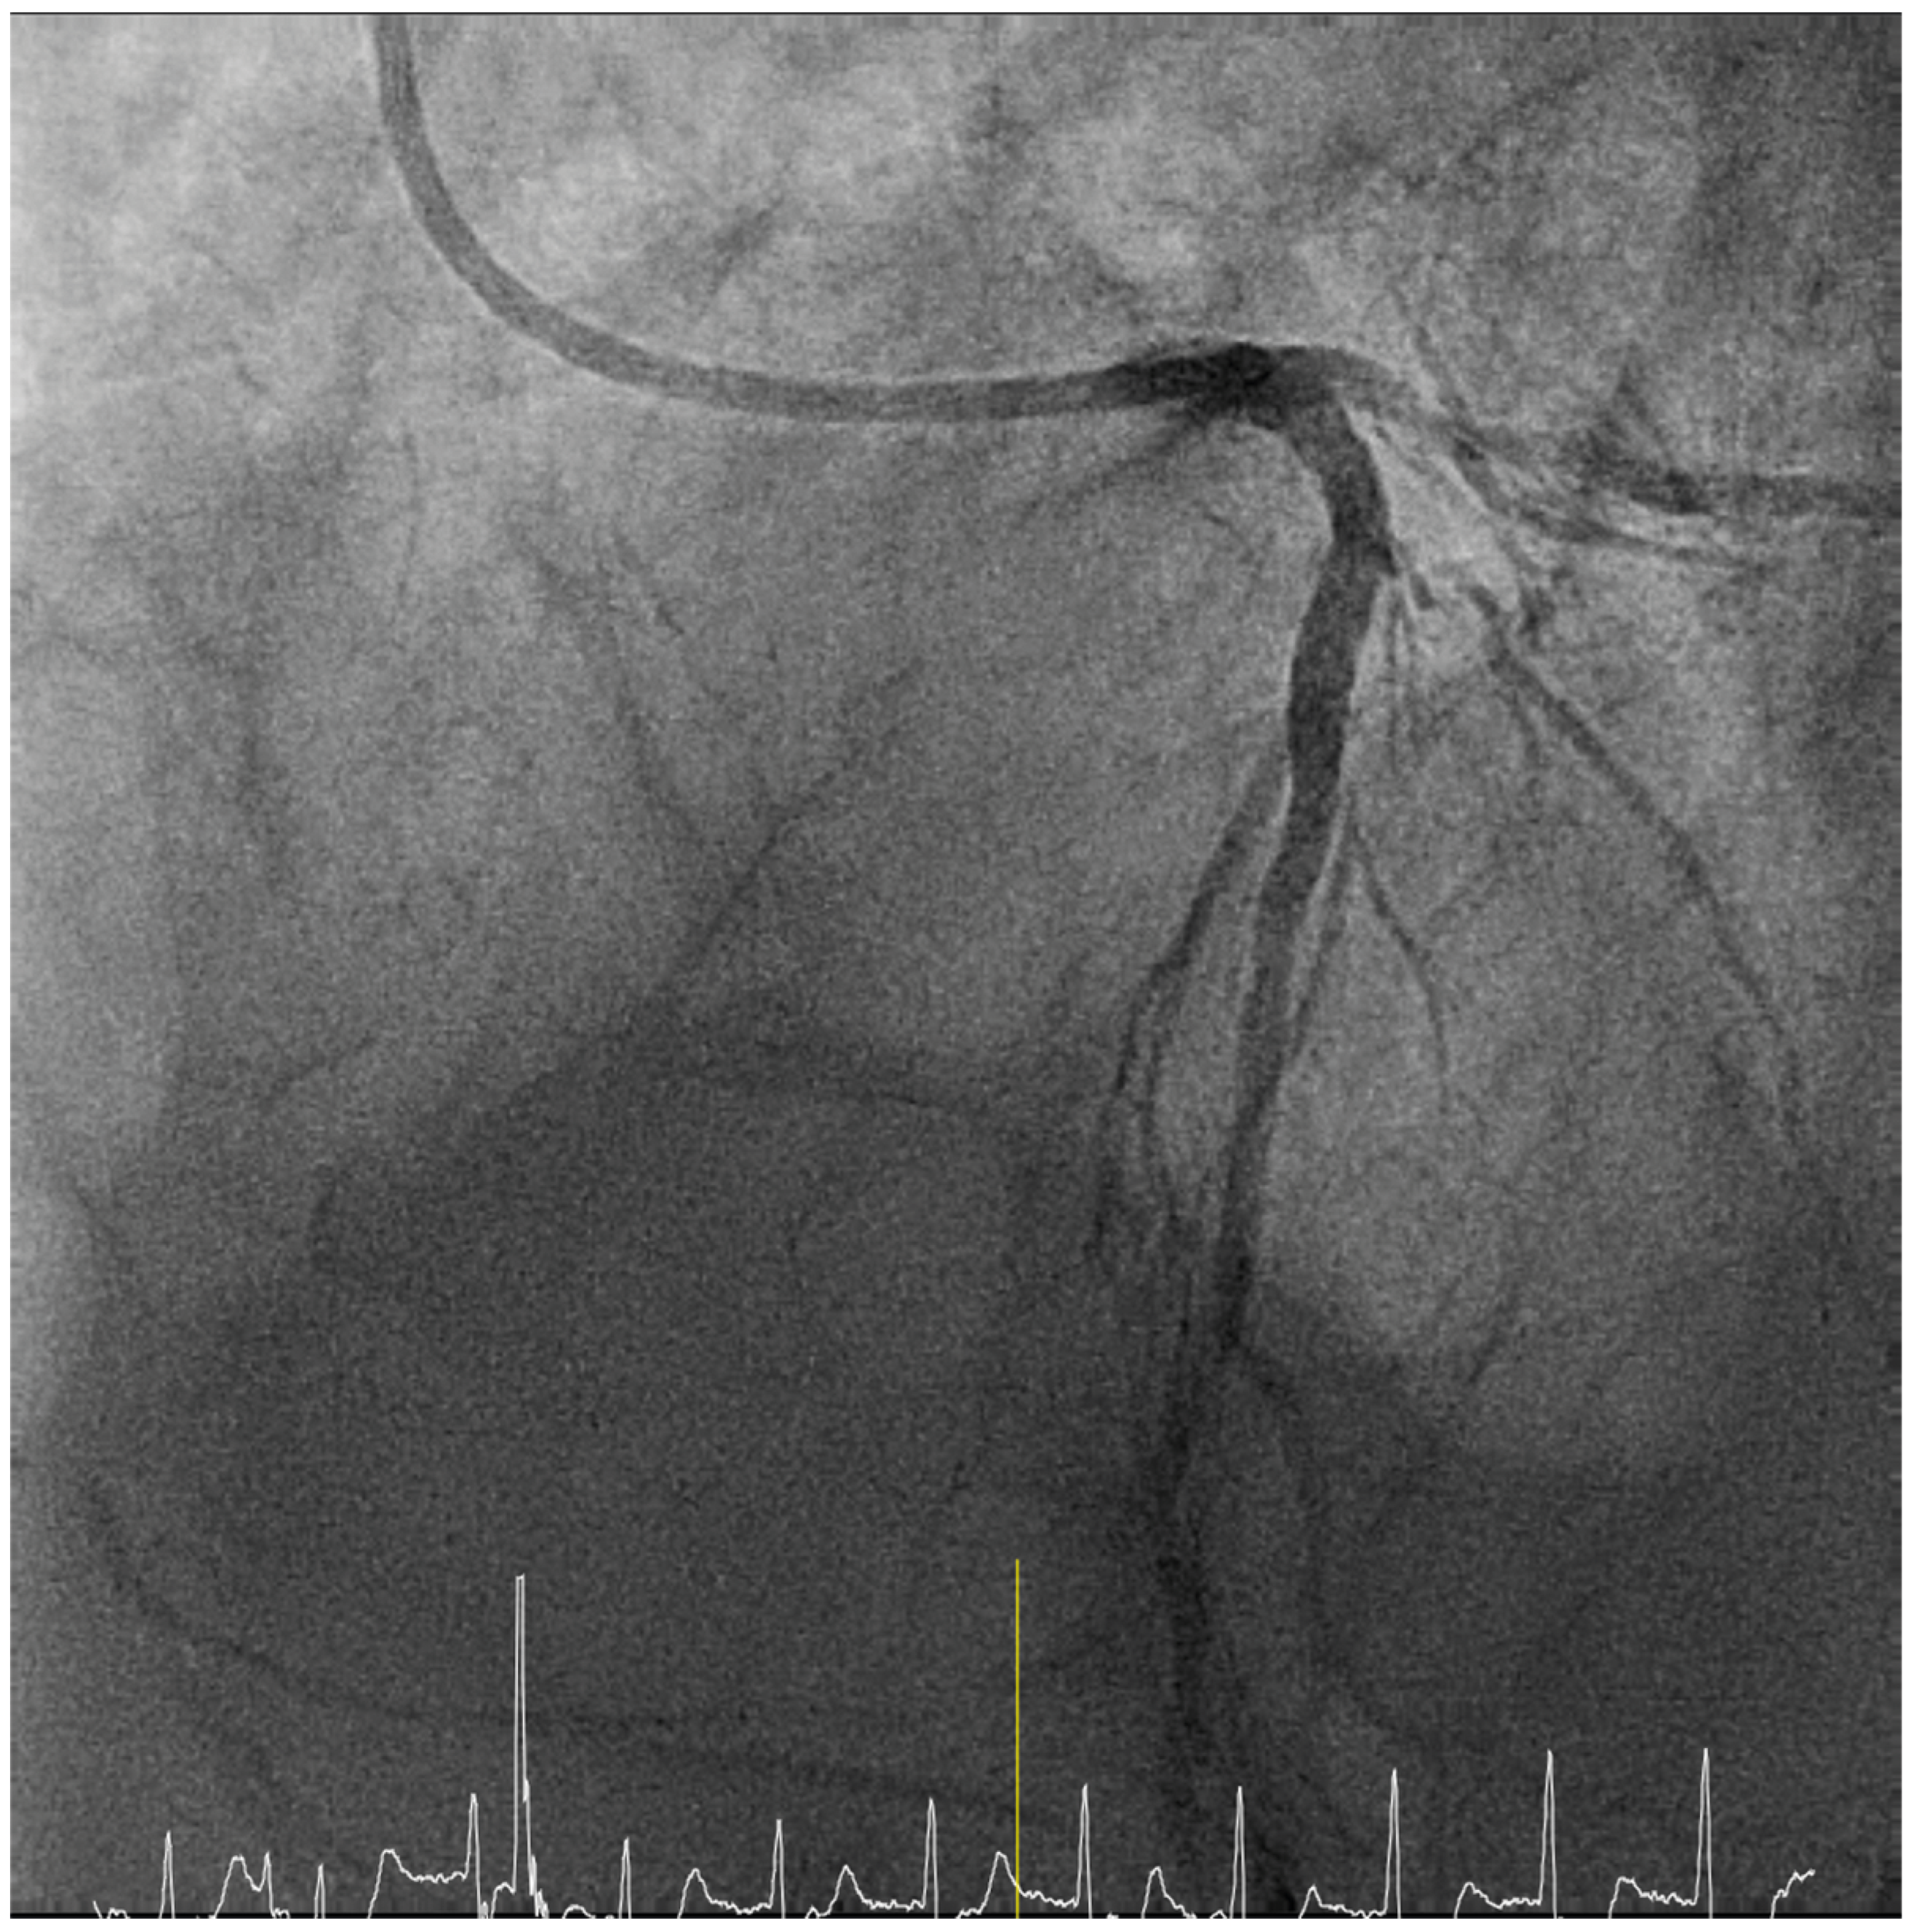

Case presentation

Solution